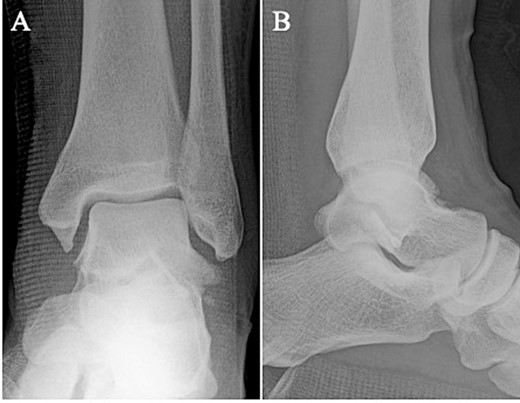

Postoperative plain radiographs showed that the bone fragment was fixed in the correct position in the anteroposterior (A) and lateral (B) views.

Postoperatively, a non-weightbearing short leg splint was postoperatively applied for 2 weeks. Active and passive range of motion exercises of the ankle were permitted at 2 weeks postoperatively. Partial-weightbearing was allowed at 4 weeks postoperatively, and full-weightbearing at 6 weeks postoperatively. The patient was allowed to jog 8 weeks after surgery. After confirming that bone union was obtained on non-contrast CT (Fig. 5) and tenderness on the lateral side of the ankle had resolved, the patient was allowed to return to his original sport at 12 weeks postoperatively. Two years after surgery, the patient remained a competitive basketball player with no symptoms. Additionally, the AOFAS score had improved to 100 points.